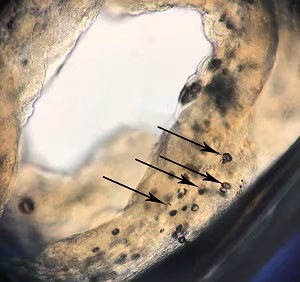

Case #493 – June, 2019

A 36-year-old male returning from a 3-month stay in rural China sought medical attention for a tender, slowly migrating nodule that had developed on his abdomen. The subcutaneous mass was excised in the clinic; a motile, ribbon-like object approximately 5 cm long was found within. The organism was placed into 10% formalin and submitted to the DPDx Team for identification. The gross morphology of the organism is shown in Figures A and B; Figure C shows the internal structure after exposure to lactophenol (100x magnification).

Figure B